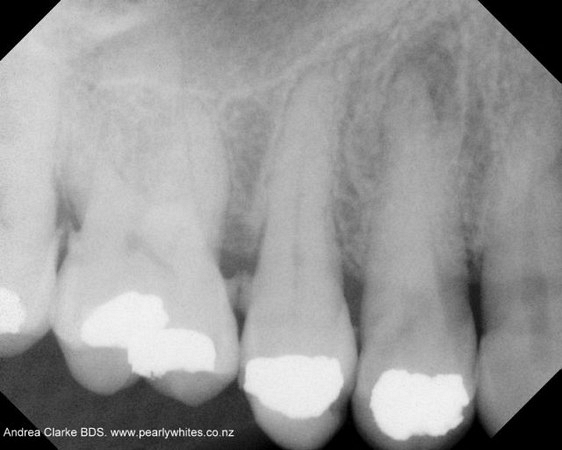

Here are examples of digital dental radiography